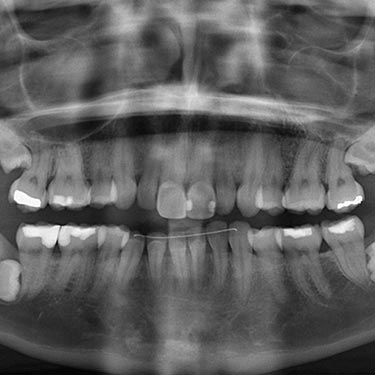

Avant tout, il faut considérer les raisons pour lesquelles on les prend. Les radiographies constituent un outil indispensable pour diagnostiquer des problèmes qu’on ne peut pas voir à l’œil nu. Notamment elles sont importantes pour voir les caries entre les dents ou sous d’anciens plombages, la position des dents de sagesse incluses, le niveau osseux entre les dents, les lésions ou infections affectant l’os, … De ce fait, un examen dentaire ne peut être considéré comme complet sans radiographies.